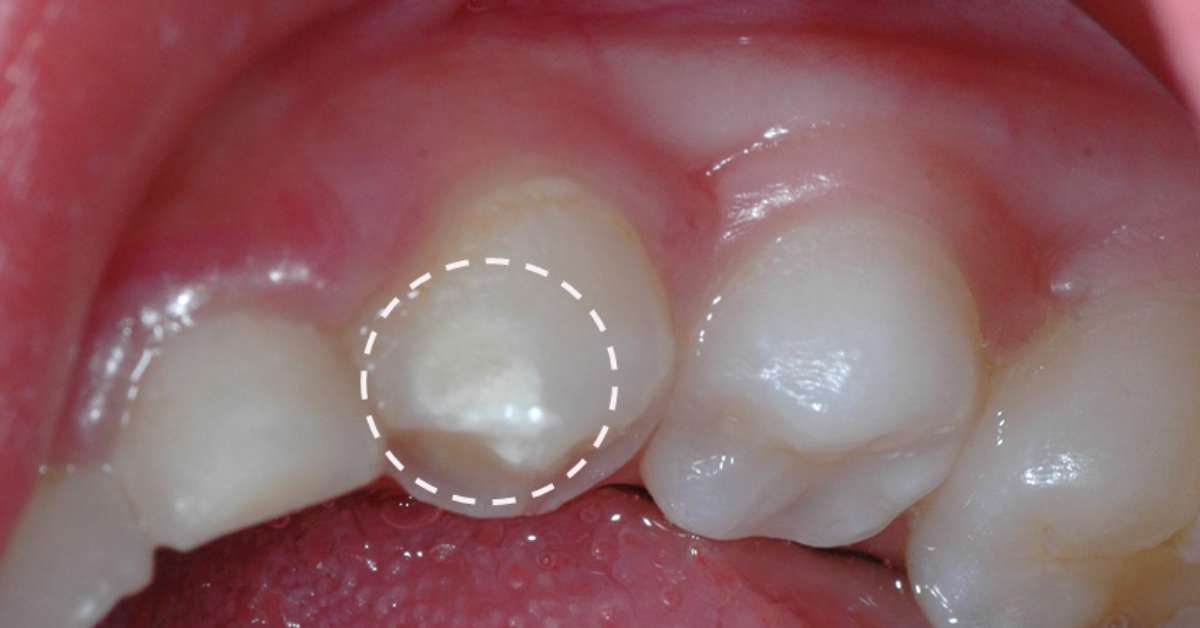

A pasta com flúor é um dos pilares na prevenção da cárie. A quantidade de um grão de arroz é suficiente e segura, mesmo para crianças que engolem. O flúor é um mineral que fortalece o esmalte dental e ajuda a remineralizar lesões iniciais.